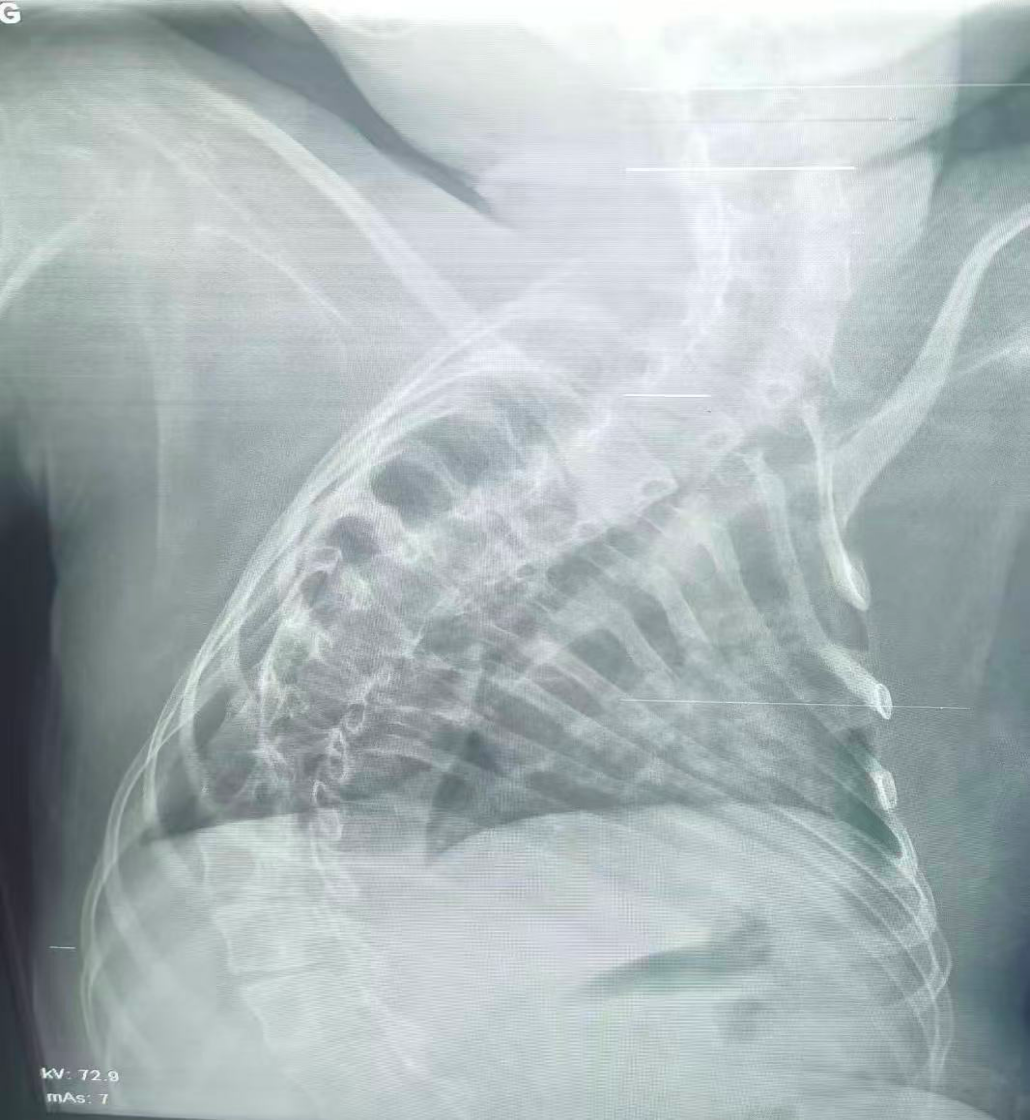

治療前

治療后